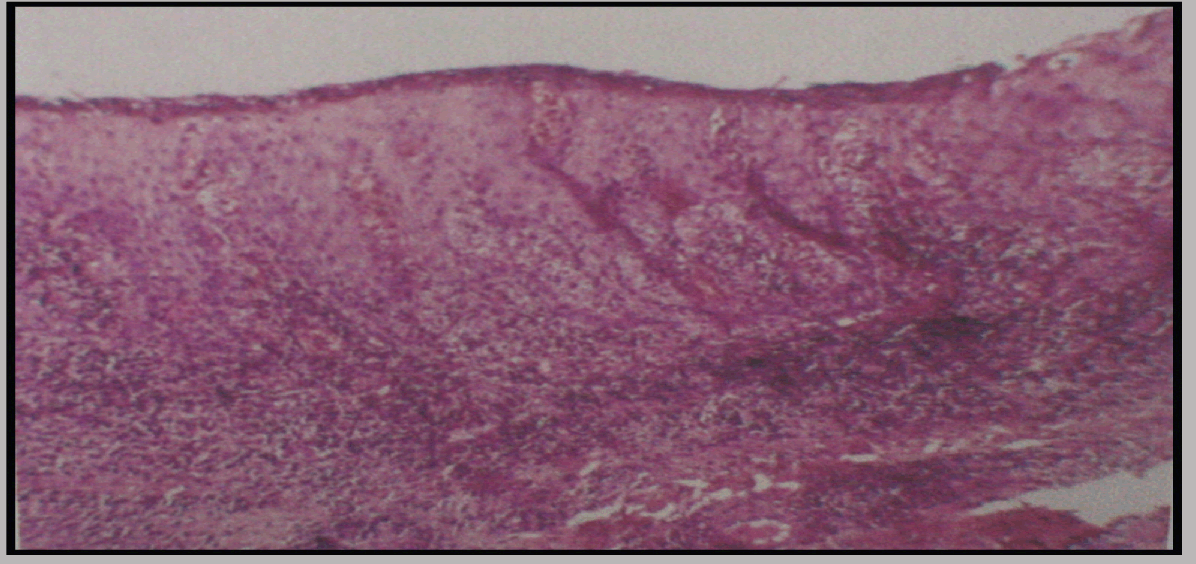

Orthopantomogram revealed severe horizontal bone loss around all the teeth. Bone loss was greater than apical third of the roots of all the teeth. Grade III furcation i.r.t 16, 26 and grade IV furcation 47. (Figure 3) Blood investigations showed normal values except for erythrocyte sedimentation rate (ESR) which was high. A biopsy was obtained, Histopathologic features showed parakeratinized stratified epithelium with elongated tube like reteridges. Epithelium over the connective tissue papillae was thinned with the proximity of the vascularized stromal tissue. Intense pooling of chronic inflammatory cells was evident suggestive of psoriasis. (Figure 4)

Cursor on image to zoom/Click text to open image

Figure 4: Biopsy showing parakeratinized stratified epithelium (H&E stain, x100)